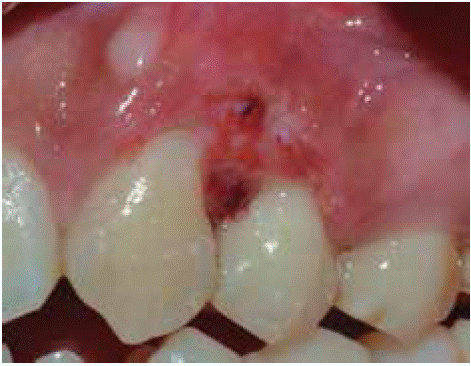

Clinical examination revealed an inflammatory gingival lesion at the level of teeth 3.4 and 3.5. Measuring approximately 15x9 mm. The lesion covered the vestibular side of the clinical crown, it was firm, lobulated, of rugged texture and bleeding upon stimulus (Figures 1and2). Periodontal assessment did not reveal periodontal pockets; presence of plaque was observed, and an O'Leary oral hygiene index of 18.75 was determined. Radiographic evaluation revealed absence of interproximal contact between teeth 3.4 and 3.5 as well as restorative material in the interproximal area (Figure 3).

Clinical examination revealed an inflammatory gingival lesion at the site of teeth 1.1 and 2.1. The lesion measured 9x9 mm approximately and covered one third of the clinical crown; the lesion was asymptomatic, firm, lobulated, of rugged texture, bleeding upon stimulus (Figure 9). Periodontal evaluation did not reveal periodontal pockets, nevertheless, presence of plaque was observed; oral hygiene index of 50% (O'Leary) was obtained.